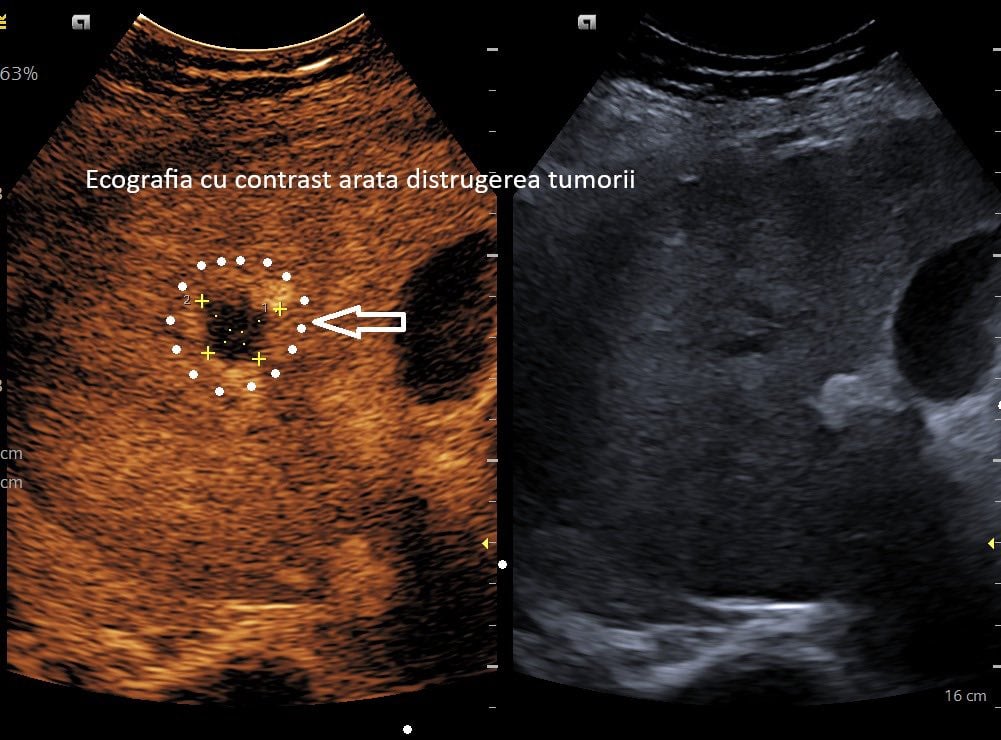

Spitalul Clinic Județean de Urgență Craiova anunță, într-un comunicat emis luni seară, realizarea primei ablații cu microunde pentru tratarea unei tumori hepatice în cadrul unității medicale. La o lună după intervenție, investigațiile imagistice au demonstrat că tumora a fost complet distrusă, conform informațiilor transmise de echipa medicală.